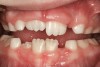

(16.) Tongues with poor tone and posture may move the teeth over time and open the bite (Case courtesy of James Awbrey, DMD).

Figure 16

(17.) Moderate adenoid swelling and significant tonsillar obstruction.

Figure 17